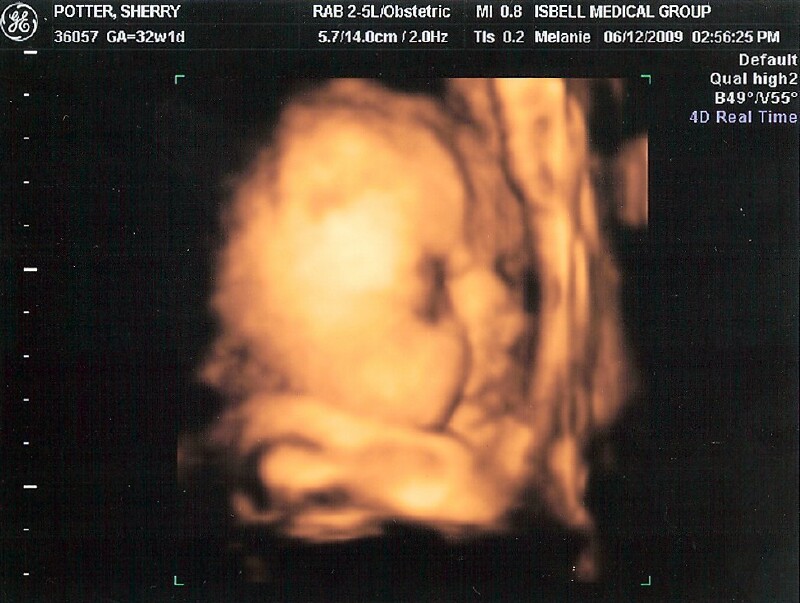

Hayley Grace June 12, 2009